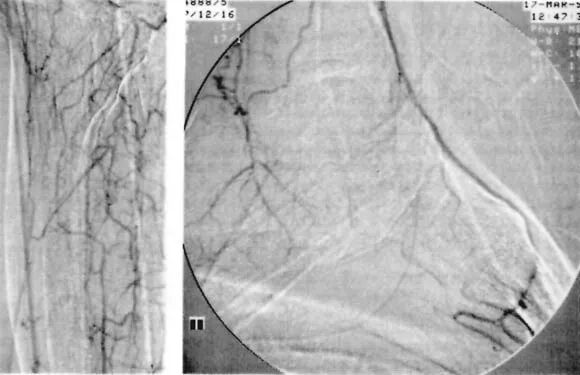

(左图)接受足背动脉旁路术患者的近端胫腓及足部循环动脉内数字减影血管造影表现:膝下腘动脉、胫前动脉与胫后动脉闭塞。腓动脉经胫腓干远端重建显影(该干闭塞)。足背动脉全程通畅,并部分充盈跖骨弓状动脉。足底动脉闭塞。

pta在医学上什么意思足背动脉旁路术:从技术革新到精准医疗_https://www.jmylbn.com_新闻资讯_第23张

腘动脉-足背动脉旁路术(采用移位非翻转大隐静脉移植)。通过近端静脉取材避免第二足部切口。